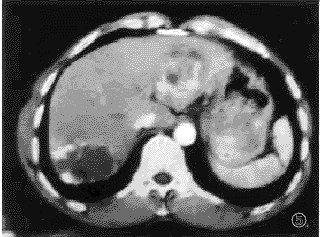

2.2.2 肝血管瘤合并肝癌多期连续扫描表现:在2例肝血管瘤合并肝癌病例,肝癌病灶数共2个,直径分别为2.5cm,4.5cm,在30秒增强时,两者表现为不均匀强化,60秒,2分钟,5分钟,10分钟,15分钟表现为低密度灶,密度欠均匀。血管瘤病灶共7个,1例为3个血管瘤合并1个肝癌病灶,另1例为4个血管瘤合并单个肝癌病灶,其中血管瘤病灶则表现为典型血管瘤强化特征。(见图5,6)。

, http://www.100md.com

图5 30秒扫描,左外叶肝癌病灶,呈不均匀强化,右的叶肝血管瘤病灶呈周围结节状强化;

图6 60秒动态扫描.肝癌病灶呈不均匀低密度区,右后叶血管瘤病灶强化向中心扩展